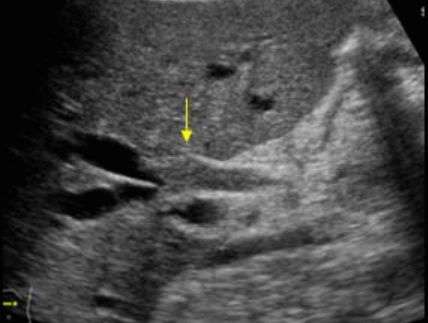

Choledocholithiasis US finding

- 총담관 내에 후방음향음영을 동반한 강한 에코가 관찰된다.

- 총담관의 확장 소견이 보인다. ( 7mm 이상)

- 담석이 관찰되지 않고 간외, 간내담관의 확장소견을 시사하는 엽총징후(shotgun sign)이나 평행관 징후(parallel channel sign)가 관찰되기도 한다.

- 엽총징후(shotgun sign): 간외 담관이 확장되어 간외 담관과 문맥이 이웃해 관찰된다.

- 평행관 징후(parallel channel sign): 간내 담관이 확장되어 인접하고 있는 문맥과 나란히 2개의 관상구조로 나타난다.